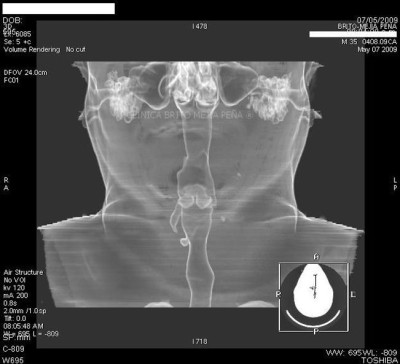

Divertículo traqueal axial

Post Image